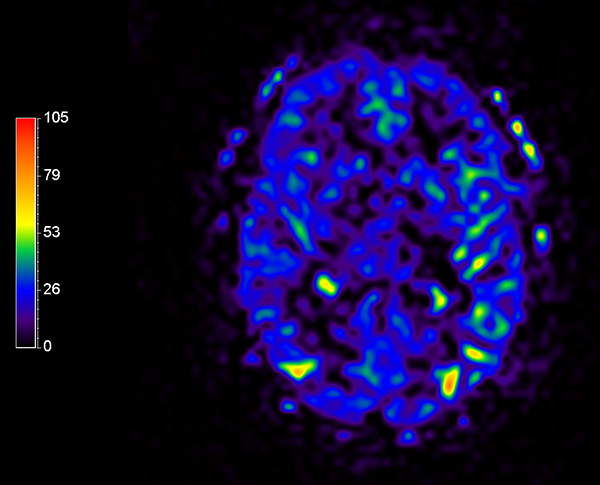

Comprehensive Brain imaging at 1.5T

Used Solution